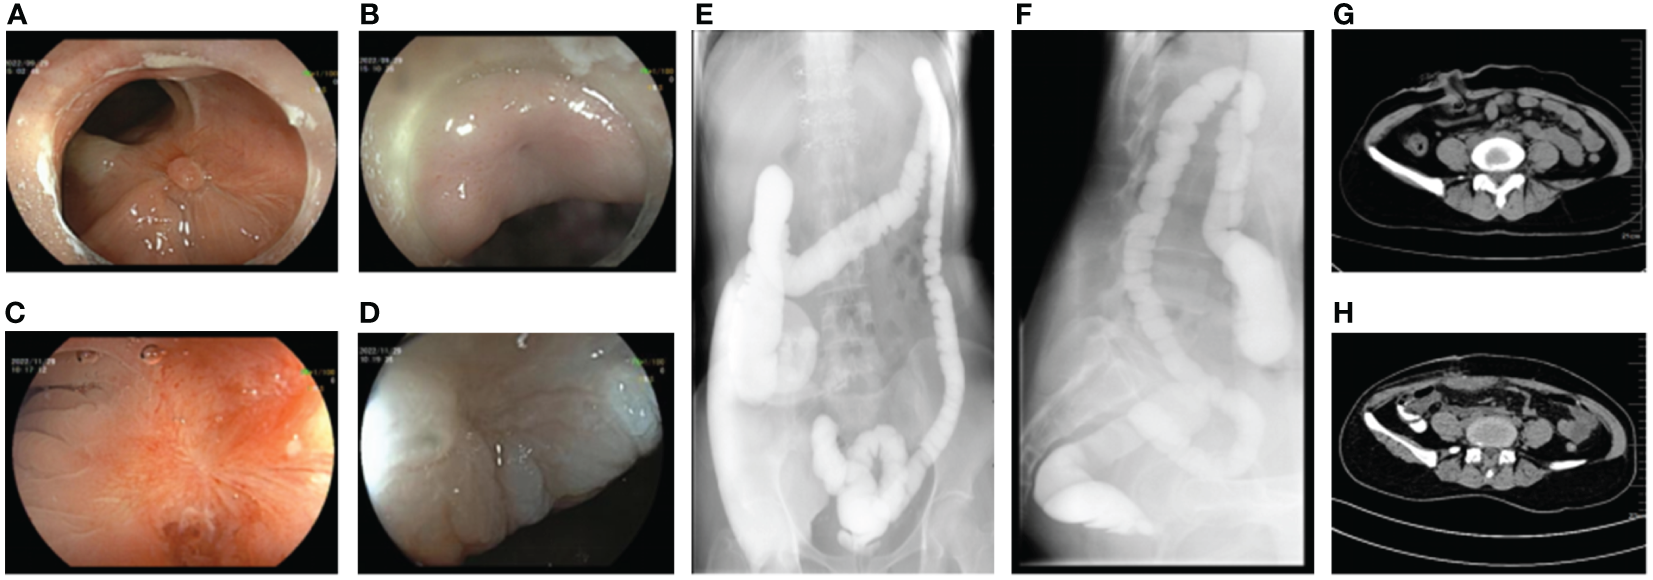

With comprehensive evaluation, the admitted patient was treated with prophylactic ileostomy and defecation diversion combined with cephalosporin antibiotics. After 7 days, there was still fecal outflow from the vagina. The colon endoscopy showed a fistula with a transverse diameter of approximately 10 mm in the anterior wall of the rectum approximately 5 cm from the anus, with significant inflammation, mucosal congestion, and edema (Figures 1A, B). The vaginal endoscopy showed a fistula in the posterior wall of the vagina, which was connected with the rectal fistula, and the suture was visualized (Figures 1C, D). A sample was collected from the edge of the fistula for histopathological examination, showing no sign of malignancy. Because only 11 days have passed since the vaginal fistula resection and layered suture repair treatment of the patient, the recovery time of the tissue was short, and the edge of the fistula was inflammatory, it was not the right time for endoscopic intervention; thus, the preventive ileostomy and defecation diversion treatment were continued. Eight weeks later, a reexamination of digestive endoscopy revealed that the mucosal inflammation at the margin of fistula was significantly relieved, and the fistula mucosa showed white scar-like changes, even though the existence of the rectovaginal fistula was still visible (Figures 1E–H). Therefore, endoscopic rectovaginal fistula repair was carried out.

Figure 1

Preoperative auxiliary examinations of the patient. (A, B) Endoscopic manifestations of rectal fistula on the first examination. (C, D) Endoscopic manifestations of vaginal fistula on the first examination. (E, F) Endoscopic manifestations of rectal fistula 1 month after ileostomy. (G, H) Endoscopic manifestations of vaginal fistula 1 month after ileostomy.